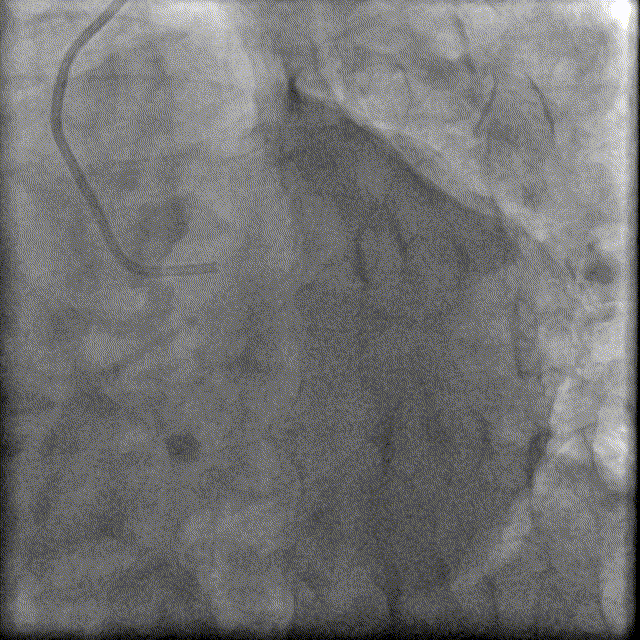

1.5×15mm、2.0×15mm、2.0×20mm、2.0×15mm Emerge球囊以10atm×15秒扩张PLA及RCA病变。

于PDA-RCA开口近段病变处植入2.5×30mm、2.75×30mm、3.0×30mm、3.5×22mm Resolute Integrity支架,2.0×15mm Emerge球囊主动拘禁保护PLA。

3.0×15mm、3.5×15mm NC Sprinter球囊以12-16atm×15秒后扩。

IVUS显示支架贴壁良好,未见夹层,RCA中远段MSA 7.41mm²,术毕。